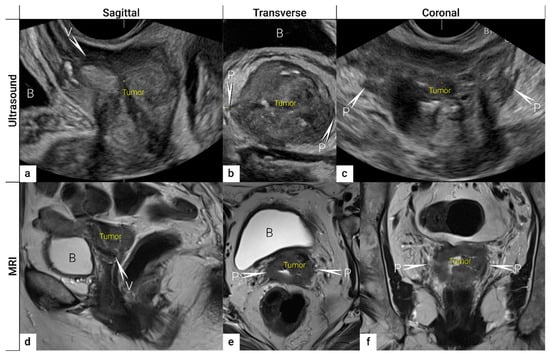

3.2. Tumour Delineation within Cervix (Tumour Size, Depth of Stromal Invasion, Minimum of Uninvolved Stroma, and Cranial Tumour-Free Margin)

| IB | Carcinoma with deepest stromal invasion >5 mm, limited to the cervix uteri with size measured by maximum tumour diameter. | US: Highly vascularised hypoechogenic (squamous-cell carcinoma) or iso-/hyperechogenic lesion (adenocarcinoma) with intact hyperechogenic pericervical fascia and positive sliding sign between tumour and bladder/rectum. MRI: Tumour has intermediate to high signal on T2W images. Dynamic CE-T1W images depicts tumour as hyperintense in the arterial phase and iso- or hypointense in the venous phase. Tumours characteristically exhibit restricted diffusion on DWI (hyperintensity on high b-value images and low intensity on the ADC maps). Tumour does not disrupt the hypointense peripheral stromal ring (best seen on T2W images). | |